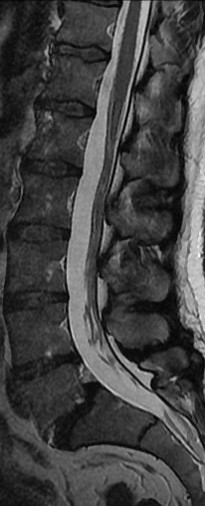

34 Yaşında Erkek Hasta

Low back pain

ODİ: %16

RM: 5/24

Ameliyat Sonrası